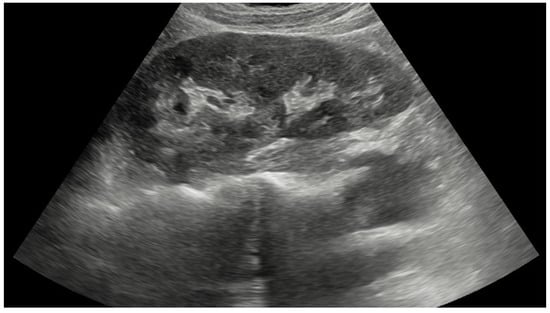

Pseudokidney sign (PKS) is a characteristic sonographic finding of an abnormal mass resembling a normal kidney (Figure 1) with a reniform appearance and a hyperechoic center surrounded by a hypoechoic area [3,4]. The sign was first reported in colorectal carcinoma [4], and since then it has been documented in many other bowel disorders such as intussusception, necrotizing enterocolitis, midgut volvulus, sigmoid volvulus, diverticulitis, regional enteritis, small bowel lymphoma, and small bowel ischemia [3,4,5,6]. However, the sign is not pathognomonic for bowel pathology because it has been seldom reported in gastric cancer [4,6]. According to Mumoli et al. [4], gastric cancer, particularly a large fungating type with eccentrically located gastric lumen and perigastric infiltration, can lead to a segmentally thickened and edematous gastric wall. Sonographically, the edematous wall is hypoechoic, and the central hyperechoic region is created by mesentery and food, resulting in PKS. Therefore, any gastrointestinal disease that includes circumscribed and hypoechoic wall thickening around the hyperechoic lumen may lead to sonographic findings of PKS [4].

Figure 1. Ultrasound image of normal kidney with centrally located hyperechoic renal sinus surrounded by hypoechoic renal parenchyma.